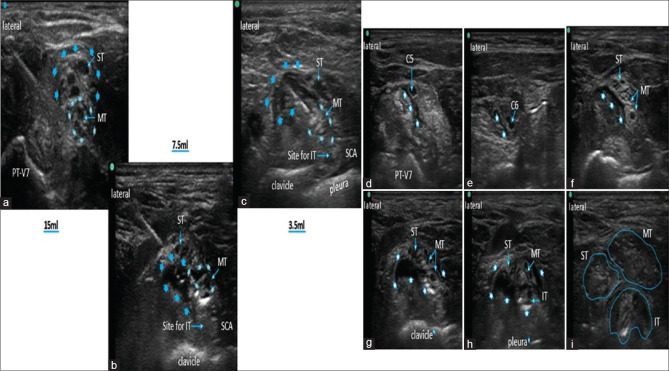

Methods: After ethics approval, ultrasound-guided injections were performed with a needle tip positioned within fatty connective tissue at the level of the MT bilaterally in 6 soft-embalmed cadavers. We injected 3.5, 7.5, and 15 ml diluted methylene blue dye in 2 cadavers each. Bilateral neck dissections were performed in the posterior triangle of the neck 30 min after injection in all cadavers to visualize the dye spread.

Results: Injection of the lower volume of dye (3.5 ml) spared the superior trunk, suprascapular and phrenic nerve (except 1 specimen), while an injection of the higher volume of dye (15 ml) consistently stained all trunks after a single injection at MT level. Similarly, the suprascapular and phrenic nerves were congruously stained with 15 ml injections, while with 7.5 ml 50% times, the PN was soaked. Dye dispersion in cadaveric brachial plexuses was deep with 15 ml and mild-to-moderate stain pattern with others.